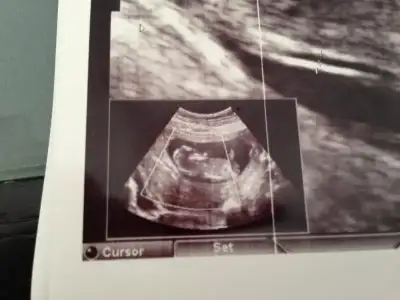

$IMG_0799.webp $IMG_0800.webp $IMG_0801.webp $IMG_0798.webp Merhaba arkadaşlar bende aranıza yeni katıldım.12 Haftalık hamileyim konuyu okuyunca dayanamadım yükledim resimleri.Bakarmısınız sizce ne olabilir bebişimin cinsiyeti

Kızlar fotograflar net deil doktorumuz bu konuda çok iyi değil güzel resim çekemiyor :1: ama gördgüğünüz kadarıyla tahmin söylersniz sevirinim :40::40: tşk :46: